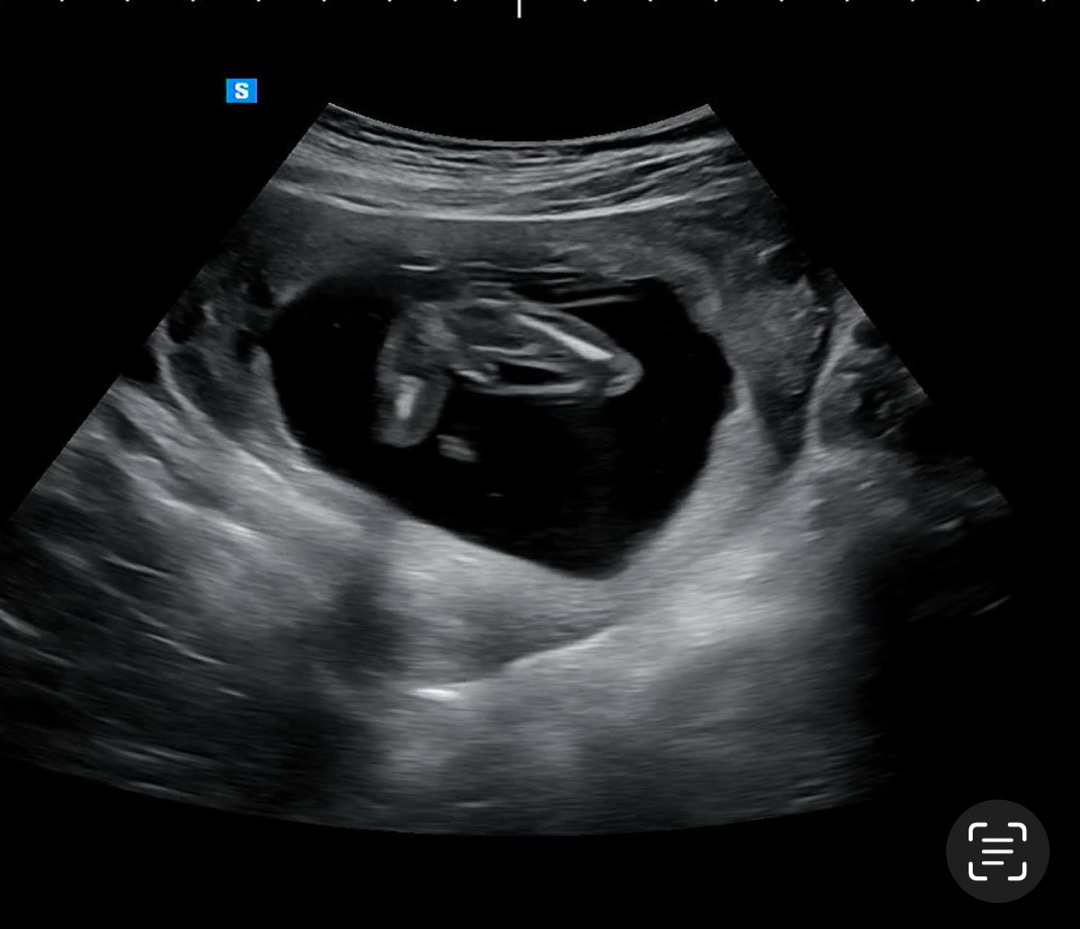

저거 고추 맞죠?

니프티로 아들인거 이미 알았지만, 성염색체 이상 소견이 보인다고해서 ㅎㅊ 융모막 검사 진행 후 1차결과 정상이라고 들었어요. 얼마나 다행인지… 초음파로 성기 확인도 잘 못했어서 더 조마조마했는데 어제 이렇게 뾱 보여주네요. 워낙 휙 지나가는 영상에서 제가 캡쳐한거지만.. 저거 고추 맞는거겠죠???